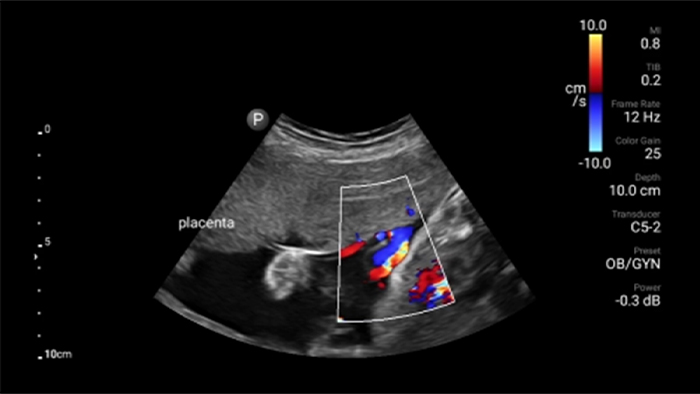

Lumify S4-1 broadband phased array transducer

• 4 to 1 MHz extended operating frequency range • 2D, color Doppler, M-mode, advanced XRES and multivariate harmonic imaging • High-resolution imaging for abdominal and cardiac applications: Cardiac, OB/GYN, Lung, Abdomen and FAST imaging preset optimizations